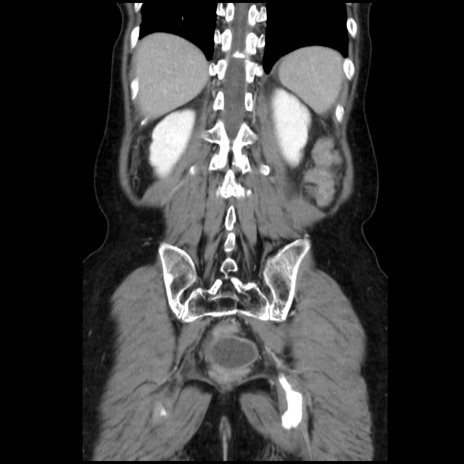

症例32(冠状断像)

【症例】40歳代 女性

【既往歴】子宮頚癌(広汎子宮全摘術、放射線療法)、腸閉塞

【身体所見】腹部:平坦、軟、腸雑音亢進、上腹部を中心に腹部全体に圧痛あり。

【データ】WBC 8400、CRP 0.03